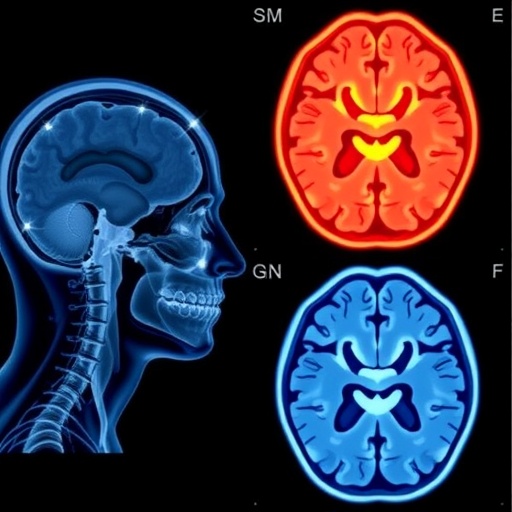

Dr. Bredel’s keynote presentation, entitled “Precision Without Incision: The New Era of Functional Radiosurgery,” emphasized the transformative potential of integrating advanced imaging modalities with radiosurgical techniques. By employing high-resolution connectomics—the comprehensive mapping of neural connections—clinicians can now tailor radiation treatments with unprecedented accuracy. This approach minimizes collateral damage to healthy brain tissue while maximizing the destruction of targeted pathological areas, thereby enhancing both efficacy and safety.

The core of this methodology lies in the convergence of several cutting-edge technologies. High-definition magnetic resonance imaging (MRI), diffusion tensor imaging (DTI), and functional MRI (fMRI) provide multidimensional maps of the brain’s functional and structural networks. When combined with stereotactic radiosurgery platforms, such as Gamma Knife and CyberKnife, these imaging technologies facilitate the delivery of concentrated high-dose radiation to precise locations within complex neural circuits implicated in movement disorders like Parkinson’s disease, essential tremor, and dystonia.